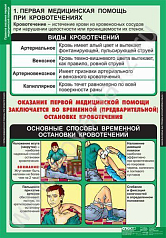

- Первая помощь при кровотечениях;

Комплект плакатов "Правила оказания первой медицинской помощи" представлены на 14-ти листах.

Материал: плотный полиграфический картон 250-280 гр./м2. Печать односторонняя. Мелование одностороннее. Красочность 4+0 (полноцвет).